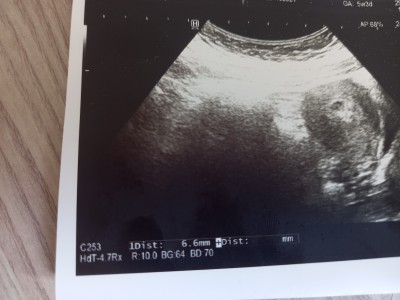

Merhaba kizlar ultrasyon yapildi keseyi gördük sizce sknti varmi bebek gorunuyomu ben pek anlamadim ama yardimci olabilirmisiniz acaba ? Randevuda bulamadim

Kasiklarim agri yapiyo oyle kanamam falan yok cok sükür ama korkuyorum 2 düsük yapmis biri olarak :(

Gebelik haftası 6

Canım kesen daha 6.6 mm yani bebeğin oluşması için çok küçük. Bir 10 gün sonra görürsun inşallah kötü düşünme ❤️

Maşallah kesen ne güzel gozukmus sanki orda yolk sac da görüyorum tam emin olmamakla beraber inşallah sağlıcakla kucağına alirsin